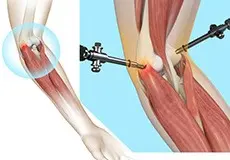

Tennis elbow Surgery

Tennis elbow is a common name for the elbow condition lateral epicondylitis.